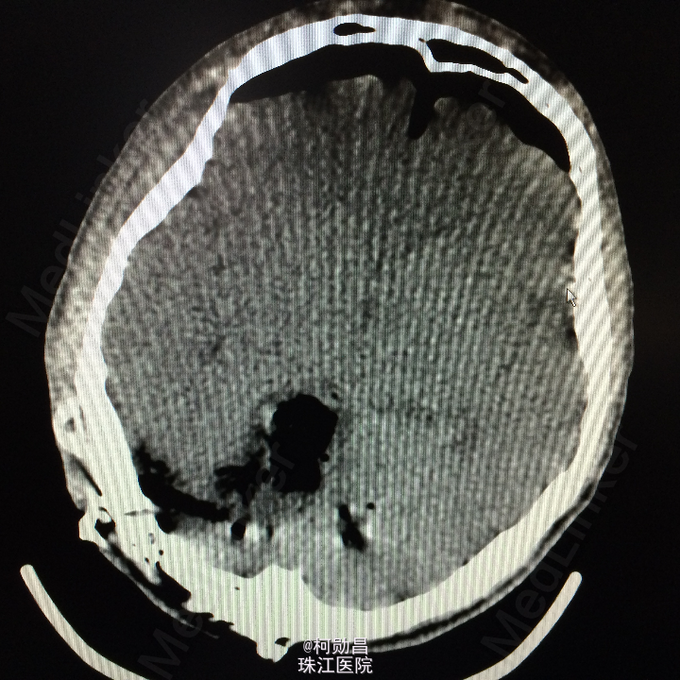

患者17岁男性,因“发现后颅窝占位1周”入院, 于1月前无明显诱因出现头晕、头痛,伴呕吐、肢体抽搐及行走不稳,无肢体乏力、意识障碍、视物模糊等,间至当地医院治疗,症状可缓解,1周前出现上述症状加重,遂至当地医院治疗,行头颅CT提示:后颅窝占位、梗阻性脑积水。后入我院,行手术治疗。病理结果提示:血管母细胞瘤